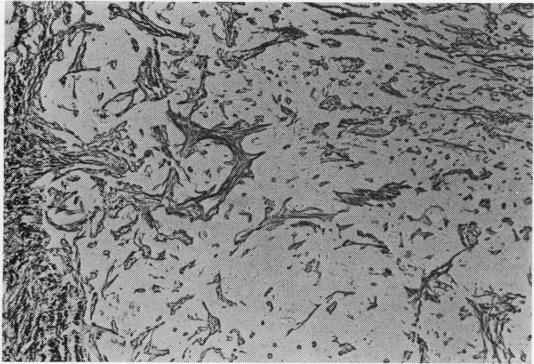

Tracheal tumours were removed surgically from two patients and diagnosed as carcinoid tumours by routine light microscopy. At a later date, electron microscopy was performed on stored tumour tissue and no neurosecretory granules were found in either case. One showed features of a glomus tumour and the other of an acinic cell tumour. Only two glomus tumours appear to have been reported previously in the trachea, and no acinic cell tumours. Electron microscopy is thus sometimes of great assistance in diagnosing accurately unusual tumours of the lower respiratory tract.

从两名患者身上手术切除了气管肿瘤,通过常规光学显微镜诊断为类癌肿瘤。后来,对保存的肿瘤组织进行了电子显微镜检查,结果在两例中均未发现神经分泌颗粒。其中一例显示出血管球瘤的特征,另一例显示出腺泡细胞癌的特征。此前气管中似乎仅报道过两例血管球瘤,而未报道过腺泡细胞癌。因此,电子显微镜检查有时对准确诊断下呼吸道的罕见肿瘤有很大帮助。